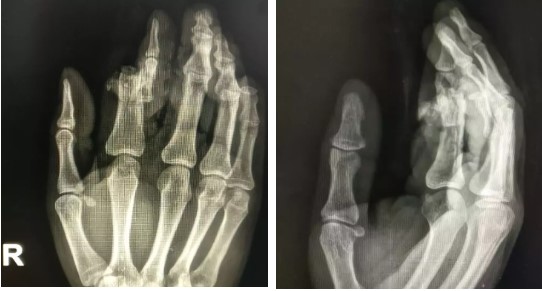

“快,去翔安医院看看还有没有机会。”在工友们的提醒下王先生被紧急送到我院,我院骨科医生检查后发现:患者右手食指自中节离断仅剩一条肌腱连接,指骨粉碎、外露,软组织碾挫严重、创面严重污染,远端指体苍白。

手术医生按顺序依次进行仔细的清创,复位粉碎的骨折并应用钢针内固定,修复断裂的肌腱,在显微镜下根据条件按比例依次修剪吻合动脉、静脉及神经。由于患指为挤压伤,软组织碾损严重,每一个过程都异常困难,周大果主任医师凭借精湛的技术及极大的耐心成功完成了再植手术。